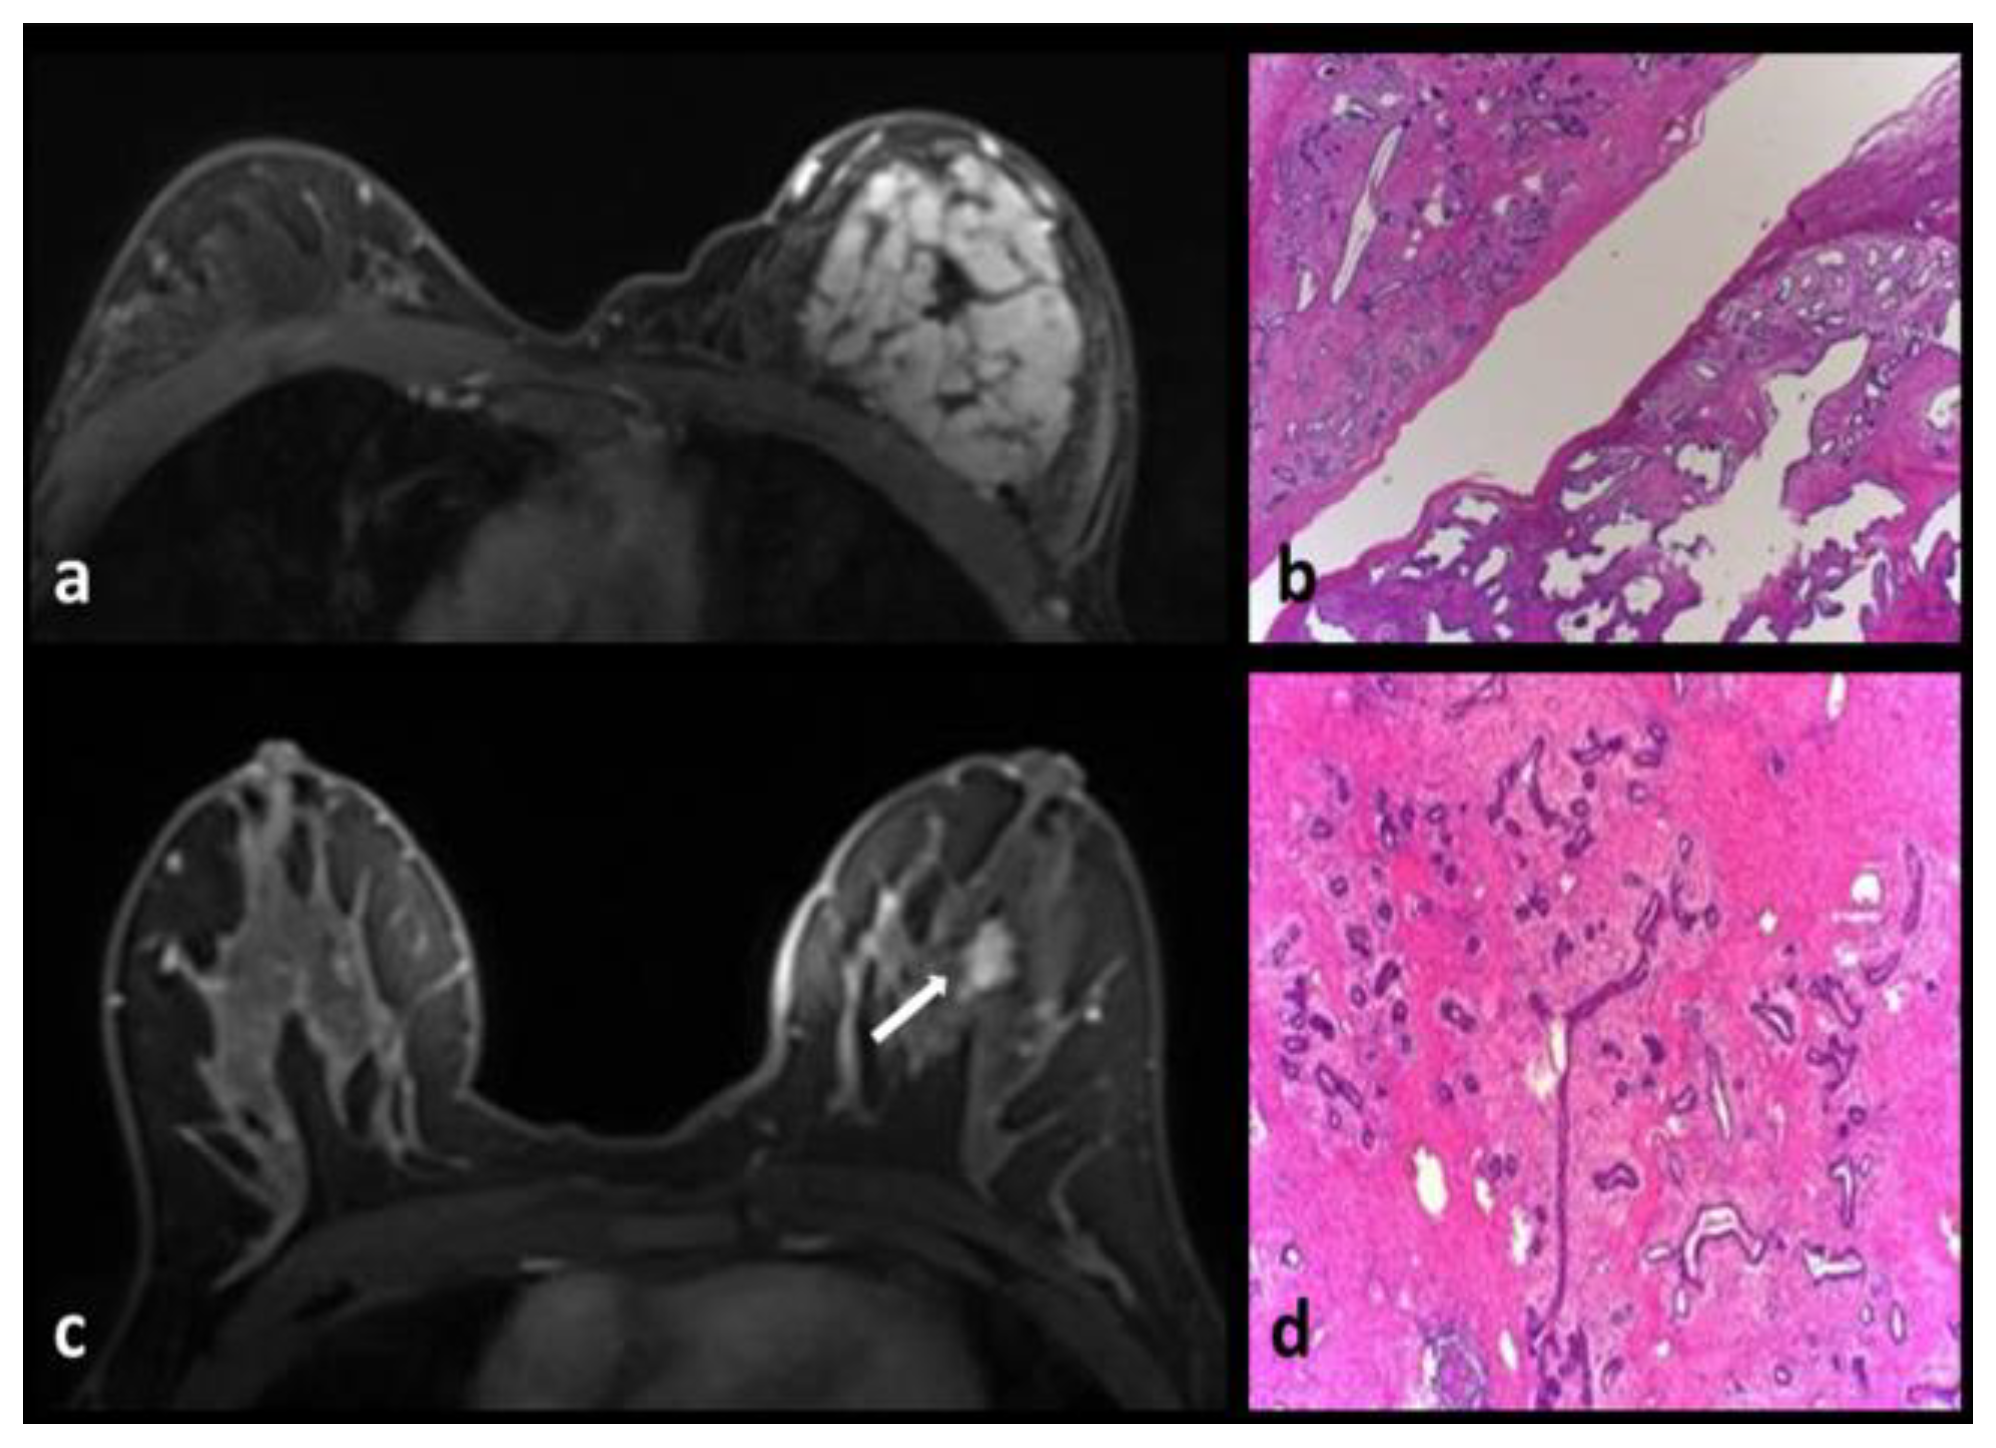

Intraductal Papilloma-Intraductal Papillomatosis